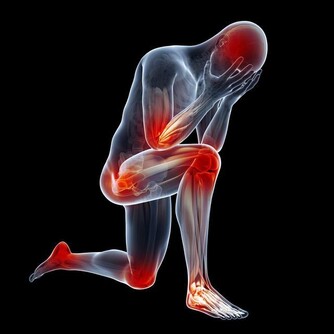

這種從肛門排出的廢氣,有時會帶有臭味;這是因為排氣時人體會釋放少量氫化硫,而這種物質具有防止細胞受損的作用,甚至可以預防心血管疾病和中風。